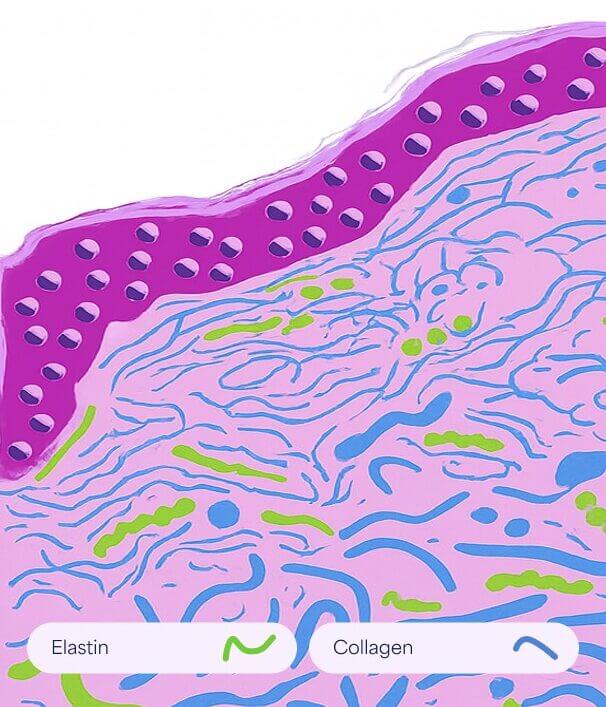

Normal Skin

Smooth and elastic with intact collagen and elastin fibers maintaining firmness and structure.

Striae Rubrae

Smooth and elastic with intact collagen and elastin fibers maintaining firmness and structure.

Striae Albae

Mature white stretch marks where collagen remodeling leads to thinning and loss of pigmentation.

How it works

- Promotes removal of damaged collagen

- Induces keratinocytes proliferation that releases growth factors to promote collagen deposition by the fibroblasts and elastin deposition

- Modulates the expression of several genes in the skin (vascular endothelial growth factor, fibroblast growth factor, epidermal growth factor, collagen type I and III) that promote extracellular matrix remodeling

This aging process is accompanied by structural and functional changes in extracellular matrix components such as collagen and elastin. The result in the appearance of fine lines and wrinkles.

How it works

- Promotes removal of old damaged collagen

- Induces keratinocytes proliferation that releases growth factors to promote collagen deposition by the fibroblasts and elastin deposition

- Modulates the expression of several genes in the skin (vascular endothelial growth factor, fibroblast growth factor, epidermal growth factor, collagen type I and III) that promote extracellular matrix remodeling